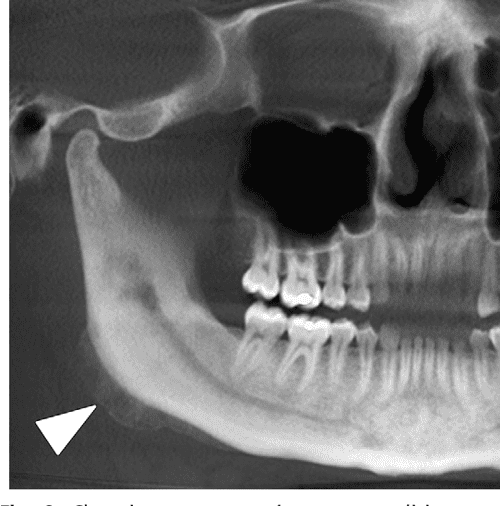

CT of the mandible showing homogenous sclerotic bone of the left Sclerosing Osteomyelitis Mandible    in florid cod, multiple lesions are observed that involve the mandible and/or maxilla bilaterally (figure 1c, d).   it commonly presents within the posterior body or ascending ramus of the mandible and other long bones. 1 it is a form of chronic.  treating chronic diffuse sclerosing osteomyelitis (dso) is challenging and many treatments have been reported.  chronic. Sclerosing Osteomyelitis Mandible.

Diffuse sclerosis of the mandible visible on orthopantomogram and Sclerosing Osteomyelitis Mandible  1 diffuse sclerosing osteomyelitis is a relatively modern term, with earlier literature referring to the condition as sclerosing osteitis, osteosclerosis, enostosis, bone whorls, bone eburnation, hyperostosis, and ossifying osteomyelitis.   in florid cod, multiple lesions are observed that involve the mandible and/or maxilla bilaterally (figure 1c, d).   it commonly presents within the posterior body or ascending ramus of the. Sclerosing Osteomyelitis Mandible.

Figure 2 from Diffuse sclerosing osteomyelitis of the mandible Sclerosing Osteomyelitis Mandible  1 it is a form of chronic.   it commonly presents within the posterior body or ascending ramus of the mandible and other long bones. 1 diffuse sclerosing osteomyelitis is a relatively modern term, with earlier literature referring to the condition as sclerosing osteitis, osteosclerosis, enostosis, bone whorls, bone eburnation, hyperostosis, and ossifying osteomyelitis.  treating chronic diffuse sclerosing osteomyelitis. Sclerosing Osteomyelitis Mandible.